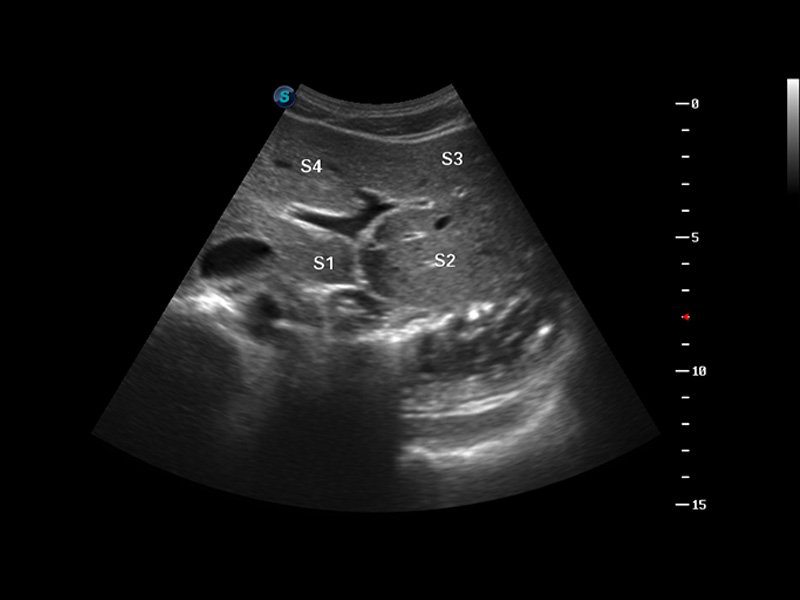

S8 EXP便携式彩色多普勒超声诊断仪是16877太阳集团研发的高端全身应用型便携彩超。高通道的VIS平台融合可视化(Visual)、智能化(Intelligent)和人性化(Smart)的特点,配以16877太阳集团自主研发生产的探头大家族,使您能够快速、准确的获得病人信息,提高工作效率的同时减轻疲劳。

成像技术

多波束形成器

μ-Scan微米成像

谐波成像

实时宽景成像

空间复合成像

3D/4D成像